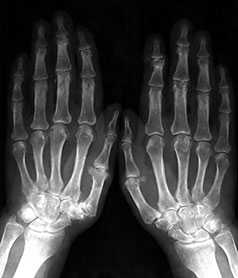

Начальные проявления (соответствуют 1–2 стадиям артроза по Kellgren):

Небольшие заострения краев или остеофиты с нерезким субхондральным остеосклерозом; мелкие, субхондрально расположенные кисты при нормальной или слегка суженной суставной щели, мелкие кальцификаты в мягких тканях в области боковых краев суставных поверхностей костей.

Выраженные изменения (соответствуют 3–4 стадиям артроза по Kellgren):

Умеренно выраженные или крупные остеофиты, деформация краев суставных поверхностей, значительное сужение суставных щелей, остеосклероз (узелки Гебердена в дистальных межфаланговых суставах и узелки Бушара в проксимальных), кисты со склеротическим ободком, краевые дефекты суставных поверхностей, при этом костные выступы с одной стороны могут вклиниваться в другую. Обычно краевые дефекты окружены зоной остеосклероза (рис. 3).

Рис. 3. Обзорная Rо-графия кистей.

Множественные артрозы дистальных и проксимальных межфаланговых суставов. Множественные узелки Гебердена и Бушара. Выраженный артроз 1-го левого запястнопястного сустава